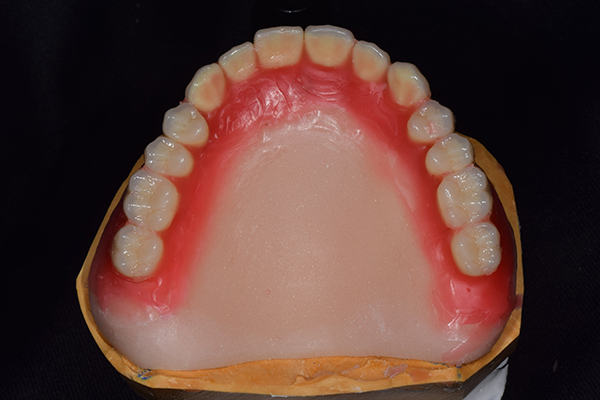

入れ歯は極力薄くするために金属を使用しました。しっかり噛める様にするため、ノンメタルクラスプデンチャーにはしませんでした。

上の入れ歯(表)

金属を使用して、薄く違和感が少ない入れ歯が完成しました。 また、見た目にも気を使い、バネが見えにくい様な構造にしました。

完成した入れ歯とかぶせ物です。 入れ歯への寛容度が高い患者様でしたので、 金属は使用せず、プラスチックのみで上は仕上げました。 下顎も歯は1本減ってしまいましたが、しっかり 入れ歯が維持できる様な構造にしました。